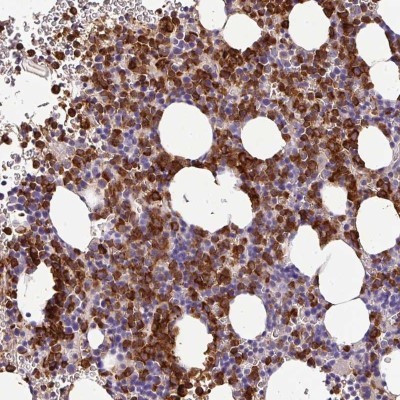

Supportive validation

- Submitted by

- Novus Biologicals (provider)

- Main image

- Experimental details

- Immunohistochemistry-Paraffin: CAB39L Antibody [NBP2-32039] - Staining of human bone marrow shows strong cytoplasmic positivity in hematopoietic cells.